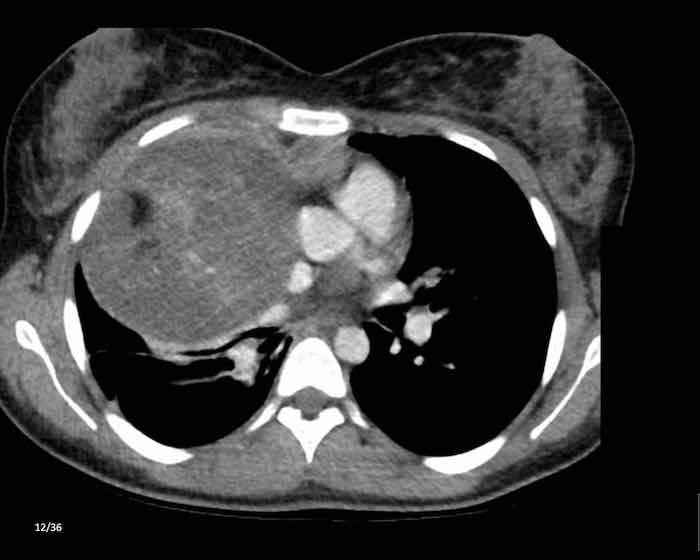

Các hình ảnh này của một nam giới 71 tuổi.

Trên CT ngực, tình cờ phát hiện một khối ở tuyến ức.

Hãy phân tích các hình ảnh. Nhận định của bạn là gì?

Hình ảnh

Một phần tổn thương có ngấm thuốc cản quang và có một số vôi hóa, có thể nằm ở thành nang.

Khi một tổn thương tuyến ức có thành phần đặc, nguyên tắc là… “khi còn nghi ngờ, hãy phẫu thuật cắt bỏ”.

Tổn thương đã được phẫu thuật cắt bỏ dựa trên kết quả CT và kết quả giải phẫu bệnh cho thấy đây là u tuyến ức dạng nang.